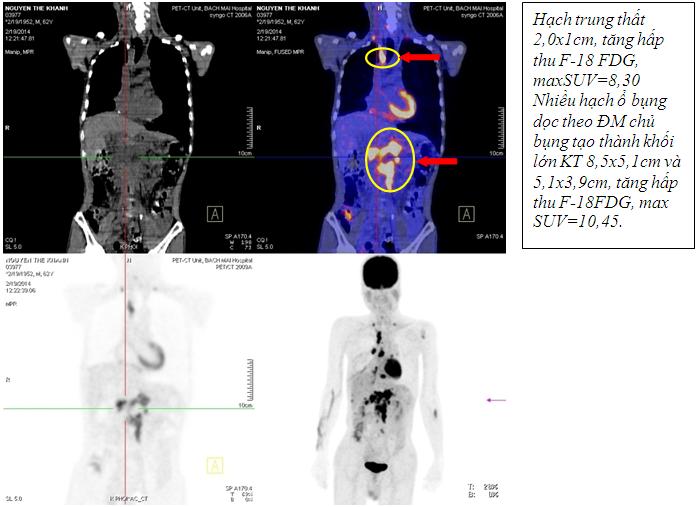

Kết quả chụp PET /CT

Kết quả chụp PET/CT: Khối vùng phế quản gốc phải KT 2,4x1,7cm; maxSUV=8,50; Hạch dưới carina KT 3,1x3,5cm ; maxSUV=8,50;Nhiều hạch ổ bụng dọc theo ĐMchủ bụng tạo thành khối lớn KT 8,5x5,1cm và 5,1x3,9cm, tăng hấp thu F-18 FDG, maxSUV=10,45; Hạch thượng đòn phải KT 1,1cm, tăng hấp thu F-18 FDG, max SUV=5,67; Hạch thượng đòn trái KT 0,8cm, max SUV=3,97; Tổn thương cung sau xương sườn số 2 bên phải tăng hấp thu F-18 FDG, max SUV=3,13; Nhu mô gan hạ phân thùy VI có nốt KT 1,2cm, tăng hấp thu F-18 FDG, max SUV=4,15.